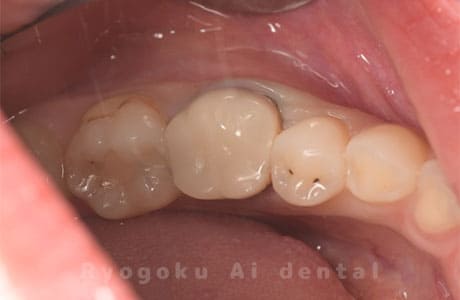

Case27

-

重度カリエス

歯牙移植咬合面術前 -

移植する親知らず

歯牙移植術直後咬合面

歯牙移植術後咬合面

歯牙移植術前側面

歯牙移植術中側面

歯牙移植術後側面

- 原因

- 重度カリエス

- 治療内容

- 自家歯牙移植、部分矯正

- 治療費用

- 220,000円(移植費用)

110,000円(部分矯正費用)

虫歯が大きく、保存不可能となった歯を上の親知らずと交換する自家歯牙移植を行いました。移植歯が小ぶりであったため、部分矯正を行い問題なく噛み合い、経過良好です。